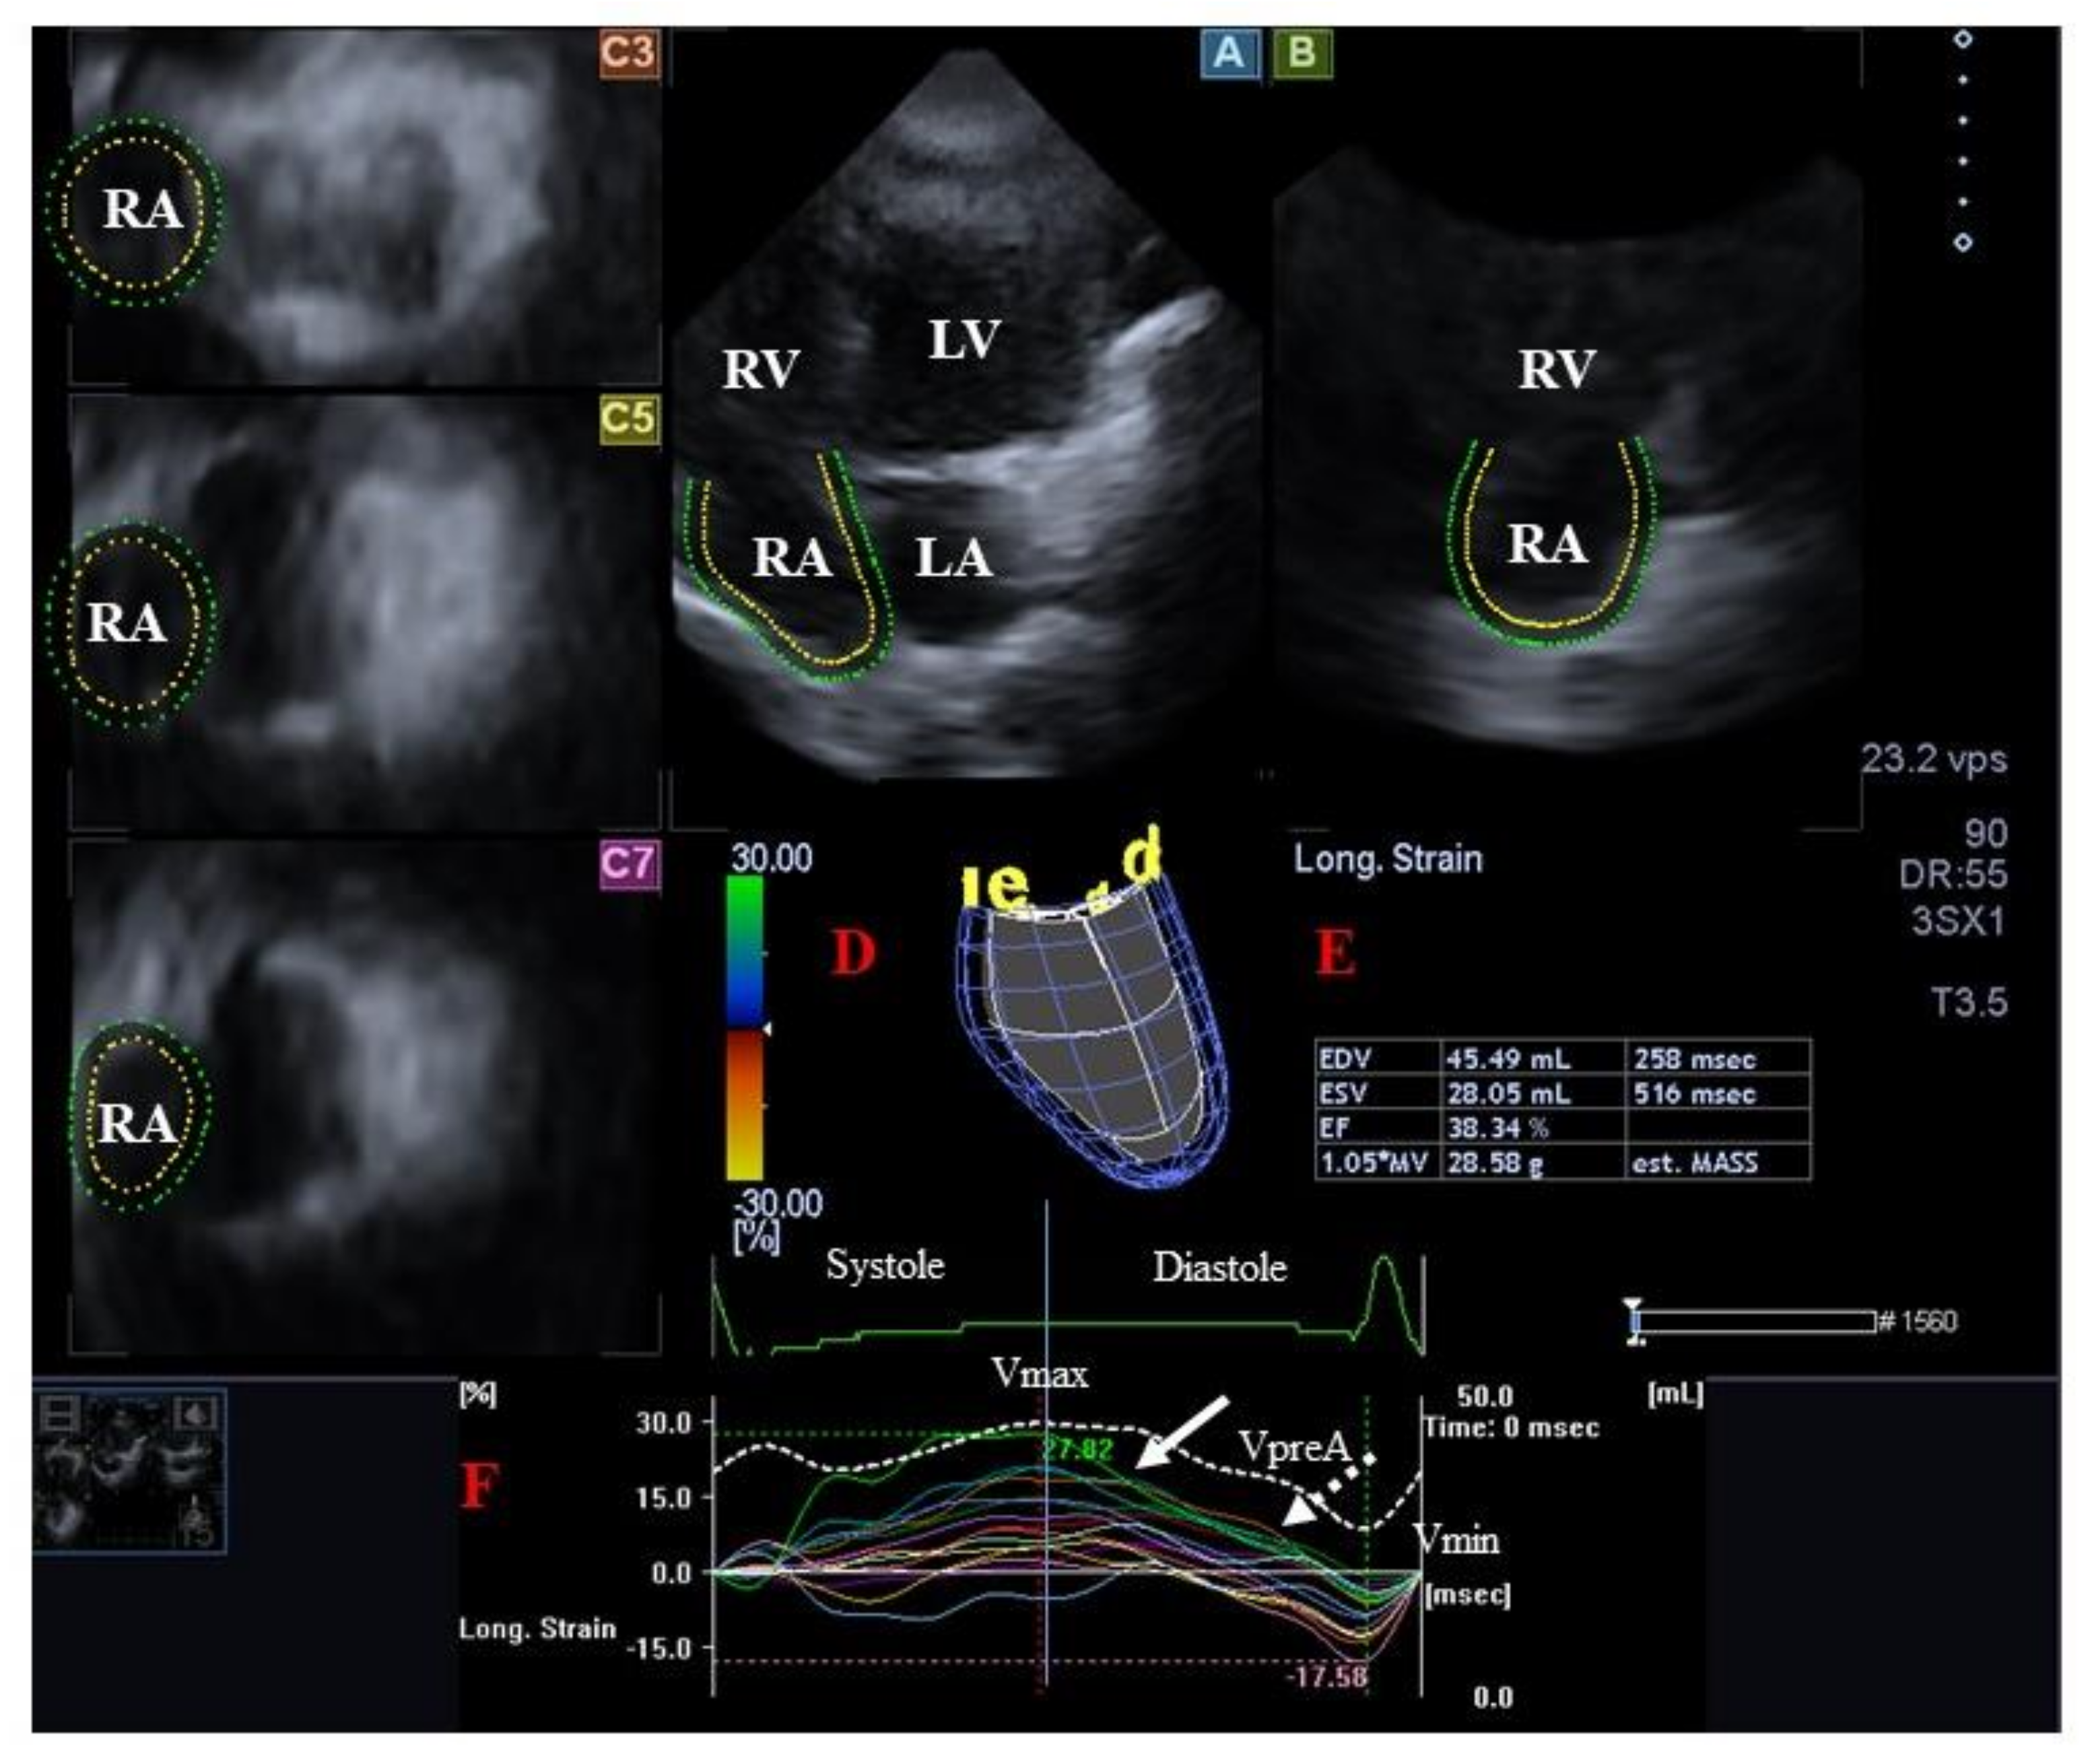

4.2. Right Atrium

4.2.1. Under Healthy Circumstances

4.2.2. In Acromegaly

- Kormányos, Á.; Kalapos, A.; Domsik, P.; Gyenes, N.; Ambrus, N.; Valkusz, Z.; Lengyel, C.; Nemes, A. The right atrium in acromegaly-a three-dimensional speckle-tracking echocardiographic analysis from the MAGYAR-Path Study. Quant. Imaging Med. Surg. 2020, 10, 646–656. [Google Scholar] [CrossRef] [PubMed]